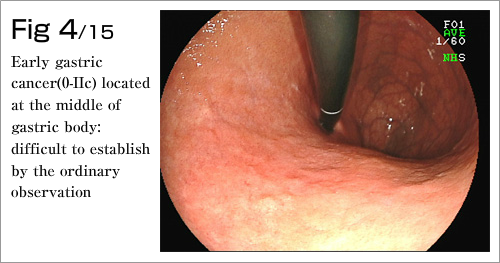

The procedure is done in several steps. First, the margins of the lesion are marked by electrocautery, and then a submucosal injection is used to lift the lesion (Diagram 4-8). After which, a circumferential incision into the submucosa is made around the lesion (Diagram 9). Finally, the lesion is dissected from underlying deep layers of GI tract wall with electrocautery knife and removed (Diagram 10-13). The lesion, mainly existing in the mucosal layer (1st layer), can be completely excised along with the submucosa (2nd layer)(Diagram 14-15).